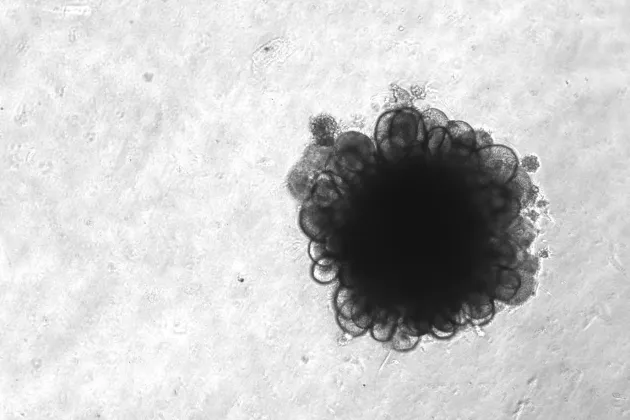

Currently, our researchers are using different types of stem cells, including induced pluripotent stem cells (iPSCs), alongside advanced technology to develop patient-specific disease models in the laboratory, called mini-organs or organoids.

These models have multiple usage areas, for example, they can be used to test drugs and to develop treatments tailored to the specific needs of individual patients.